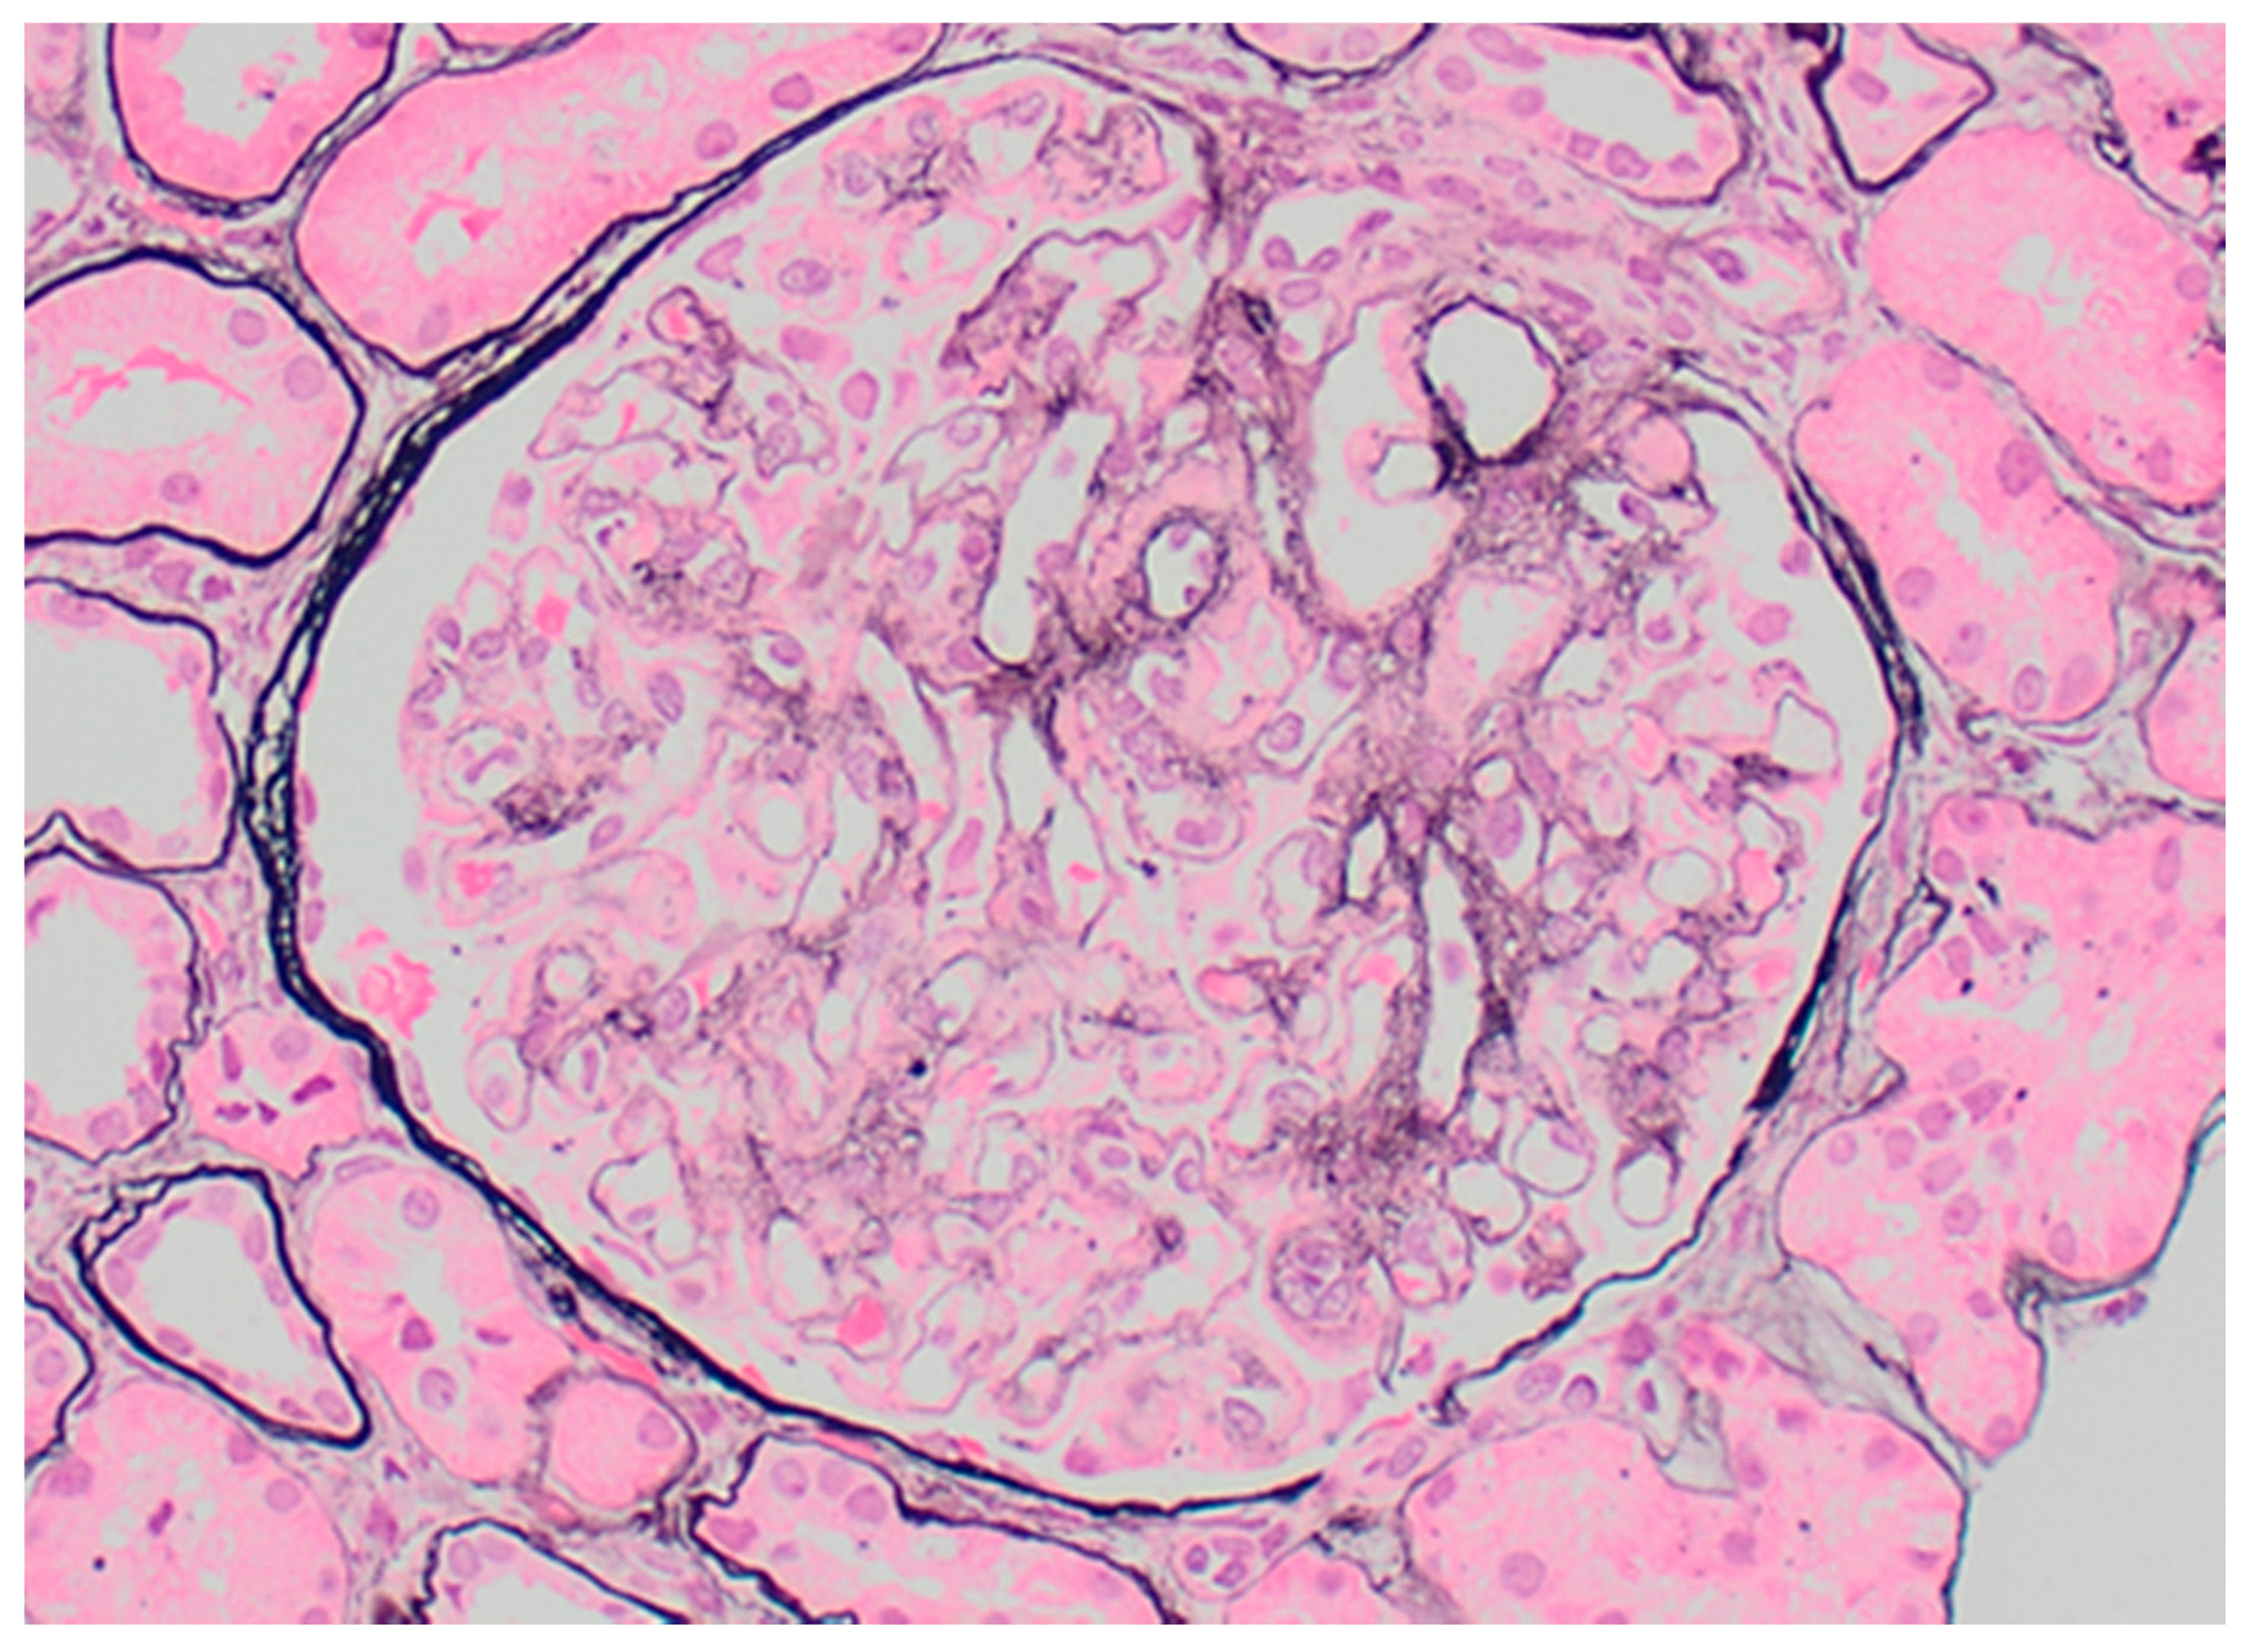

Proliferative glomerulonephritis with monoclonal immunoglobulin deposits (PGNMID-Ig) is defined on kidney biopsy as light microscopy findings of proliferative or membranoproliferative glomerulonephritis (Figure 7), with immunofluorescence or immunohistochemistry showing monotypic glomerular deposits for a heavy chain (IgG, IgA, or IGM) and an associated light chain (kappa or lambda), and electron microscopic findings of granular, glomerular electron dense deposits [106,107,108]. The lack of substructure on electron microscopy distinguishes PGNMID-Ig from immunotactoid glomerulopathy and cryoglobulinemic glomerulonephritis. IgG3 is the most common involved IgG subclass (60–70% of cases, usually with kappa light chain), followed by IgG1, IgG2 and IgG4. Cases of monotypic staining involving IgM and IgA heavy chains are also well-recognized.

On kidney biopsy, cryoglobulinemic GN (Figure 4) has an endocapillary to membranoproliferative pattern of injury, with influx of monocytes and neutrophils. Large intracapillary “plugs” of immune complexes may be present, as well as extraglomerular leukocytoclastic vasculitis. Immunofluorescence shows irregularly distributed, chunky capillary wall staining for the monoclonal protein in type 1 cryoGN, commonly IgG and one light chain, and the addition of IgM in type 2 cryoGN. Electron microscopy shows occasionally large subendothelial and mesangial deposits, some with microtubular organized substructure.